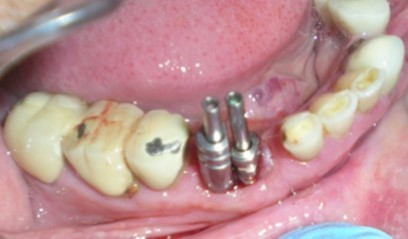

Healing abutments were cleaned and removed from mouth (Figure 2) and placed in a disinfecting solution. Direct impression coping (AlphaBio, Israel) was on one of the implants (SPI, AlphaBio, Israel) and secure it with long connecting screw (Figure 3).

Figure 3.Modified impression copings in proper position.

The other impression coping was modified by holding it with artery forcep and cut it with carborundum disc so that it fits properly over the other implant. After modification, it was secured with long connecting/fastening screw to the respective implant. the complete seating of the impression copings was verified with a periapical radiograph.